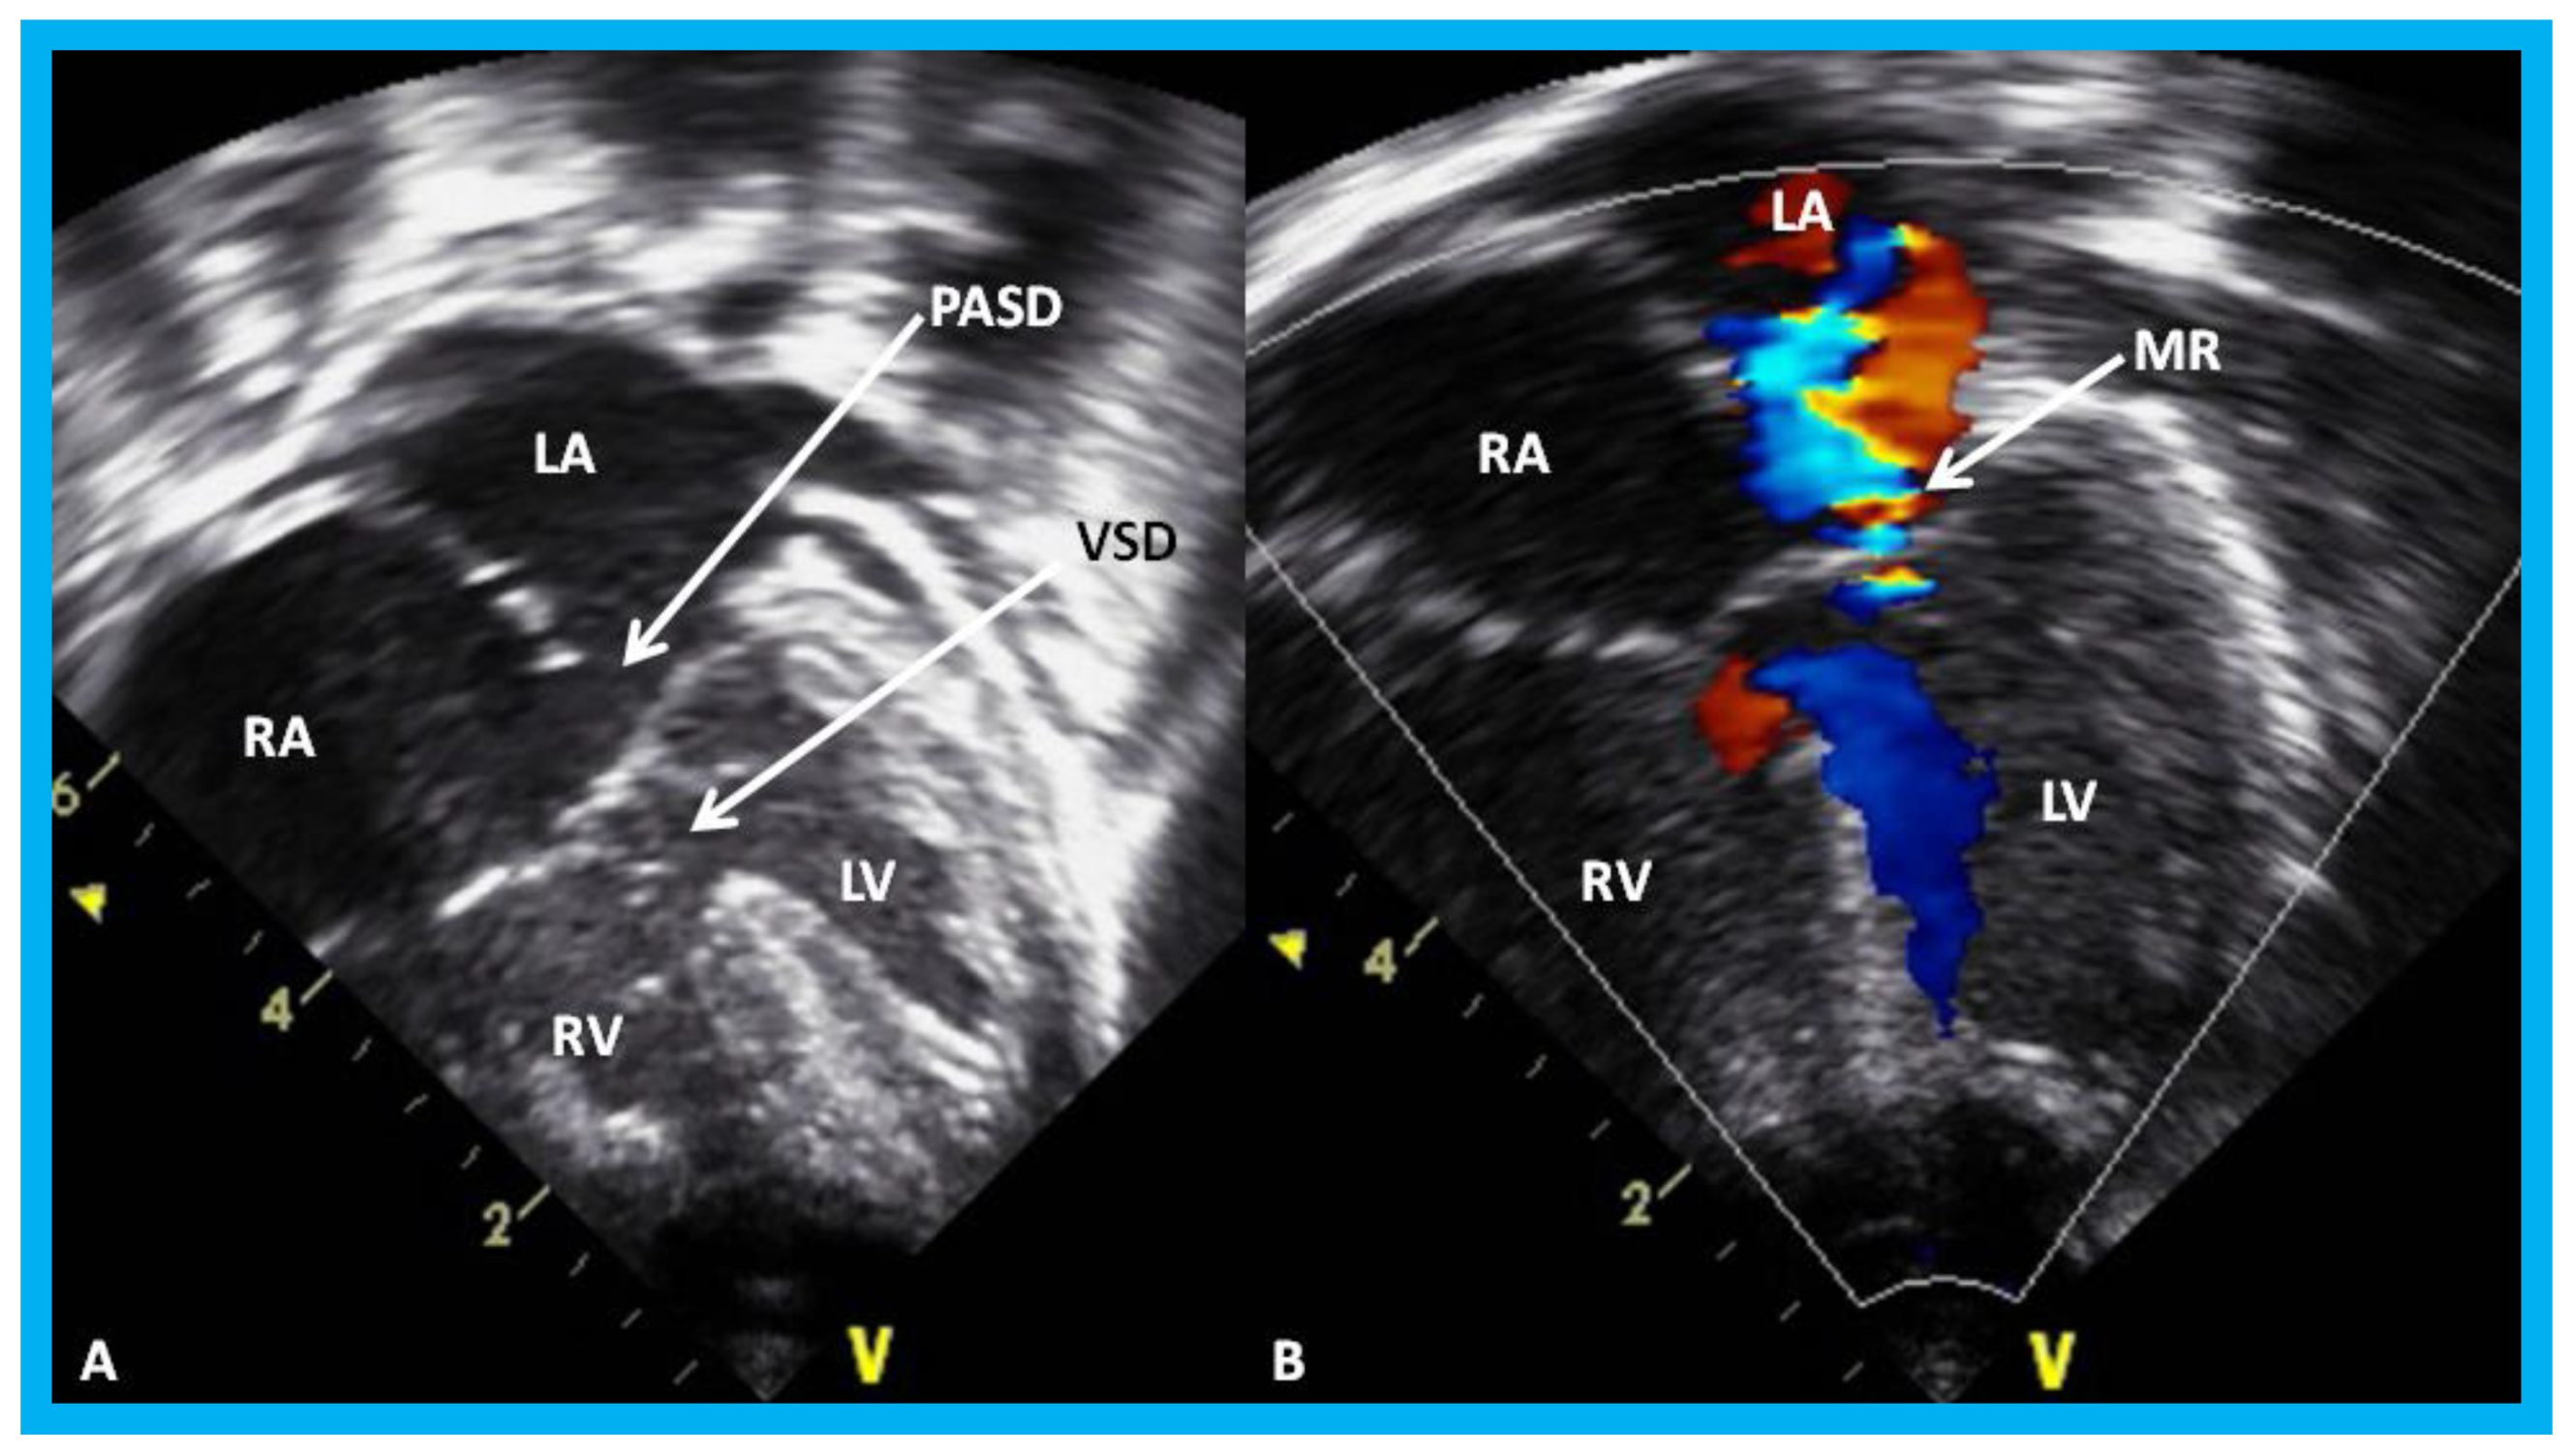

Figure 29. Apical four-chamber view of the heart in baby with Down syndrome demonstrating atrioventricular septal defect in 2D (A) and color-Doppler imaging (B): Ostium primum atrial septal defect (PASD) and ventricular septal defect (VSD) are shown (arrows) in (A) and mitral regurgitation (MR) in (B) (arrow). LA, left atrium; LV, left ventricle; RA, right atrium; RV, right ventricle.

Children 07 00034 g029